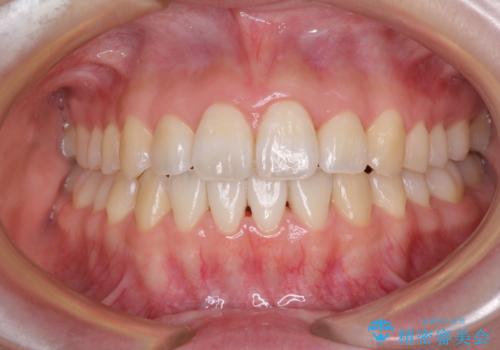

- 前歯の捻れと、ちょっとした出っ張りを気にして来院された患者様です。

歯と歯の間を削る(IPR)ことでデコボコを解消し、インビザラインで整えることとしました。

インビザライン治療特有の奥歯が接触しない時期が続き、当初予定よりも期間がかかりましたが、最終的には安定した咬み合わせと、整った前歯になりました。